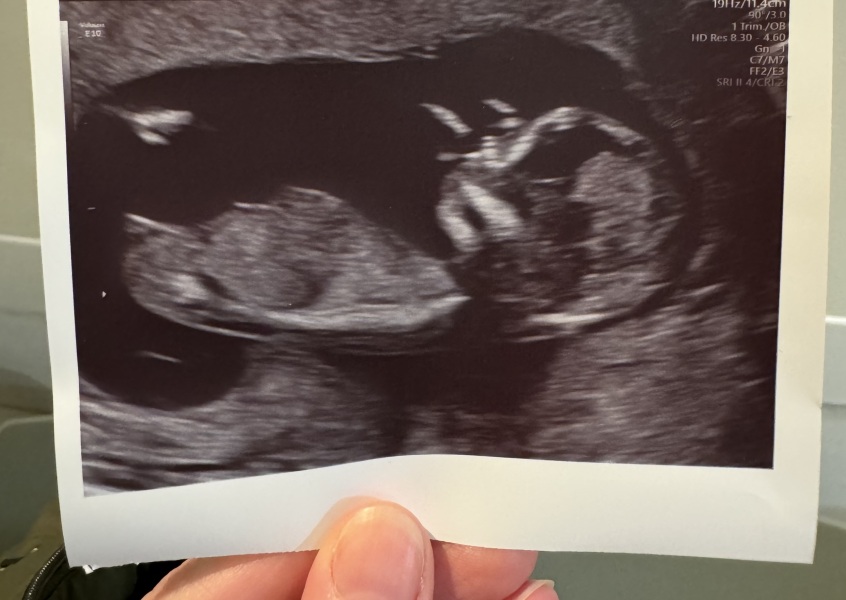

My DH gifted me a scan (🤣🙃) which I had done yesterday so also feeling really happy, I think we'll announce on the 10th which is DH's bday!

Look at that perfect baby!! @sellingupslow 🎄🎄

@JDecember21 wow!!

Your scan is amazing, always makes me laugh how their little noses look 🤣

All was good with mine too, they said looks like a low chance of chromosomal abnormalities but would confirm with bloods (which they took today)

11DPO positive - but concerned